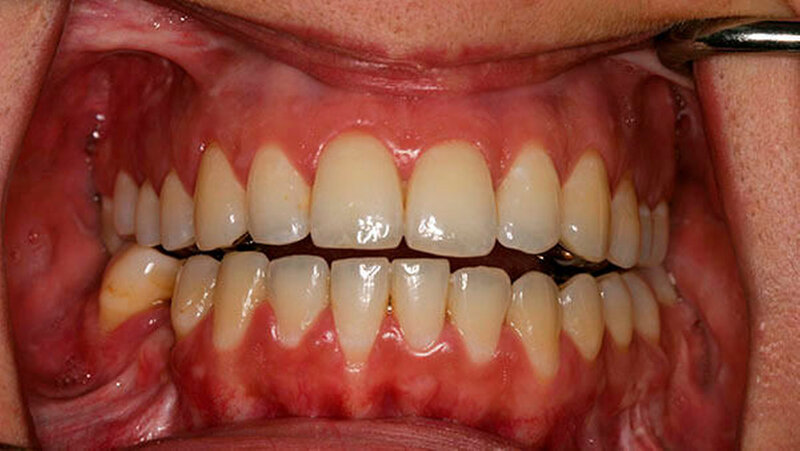

Der fortschreitende Schwund der Kiefergelenkfortsätze führte bei einer 28-jährigen Patientin zur Öffnung des Zusammenbisses von Ober- und Unterkieferzähnen und zur Rückwanderung des Unterkiefers. Sie hatte erhebliche Schwierigkeiten beim Essen und ihr Profil war dramatisch verändert (Vogelgesicht).

Die Patientin war gerade über 20 Jahre alt, als die Krankheit schleichend begann: Zunächst fiel der jungen Frau auf, dass der Kontakt zwischen den oberen und den unteren Schneidezähnen immer mehr verloren ging. Mit der Zeit wurde die Lücke immer größer, was im weiteren Verlauf ein Abbeißen unmöglich machte. Zudem bemerkte sie, dass ihr Kinn immer fliehender wurde, also immer weiter zurückfiel.

Die Patientin erreicht dauerhaft eine Mundöffnung von 35 mm ohne Schmerzen, kann jede Nahrung zu sich nehmen und hat einen stabilen Zusammenbiss der Zähne - auch die erhebliche Rücklage des Unterkiefers ist dauerhaft beseitigt.